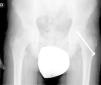

Diagnóstico por la imagenLas radiografías anteroposterior y axial de ambas caderas nos permitirán confirmar el diagnóstico. Es importante obtener la radiografía de ambas caderas por la alta incidencia de bilateralidad. En la radiografía antero-posterior y axial de ambas caderas podemos observar un desplazamiento antero-superior de la metáfisis proximal del fémur (cuello femoral) respecto a la epífisis (cabeza femoral). Denominamos signo de Steel, a la doble densidad radiográfica creada por la epífisis que se desplaza posteriormente y se superpone a la parte medial de la metáfisis (fig. 1). La línea de Klein, es una línea que se traza en la parte antero-superior del cuello femoral en la radiografía antero-posterior y que corta la epífisis. En los casos de ECF, la epífisis femoral queda por debajo de esta línea (fig. 2).